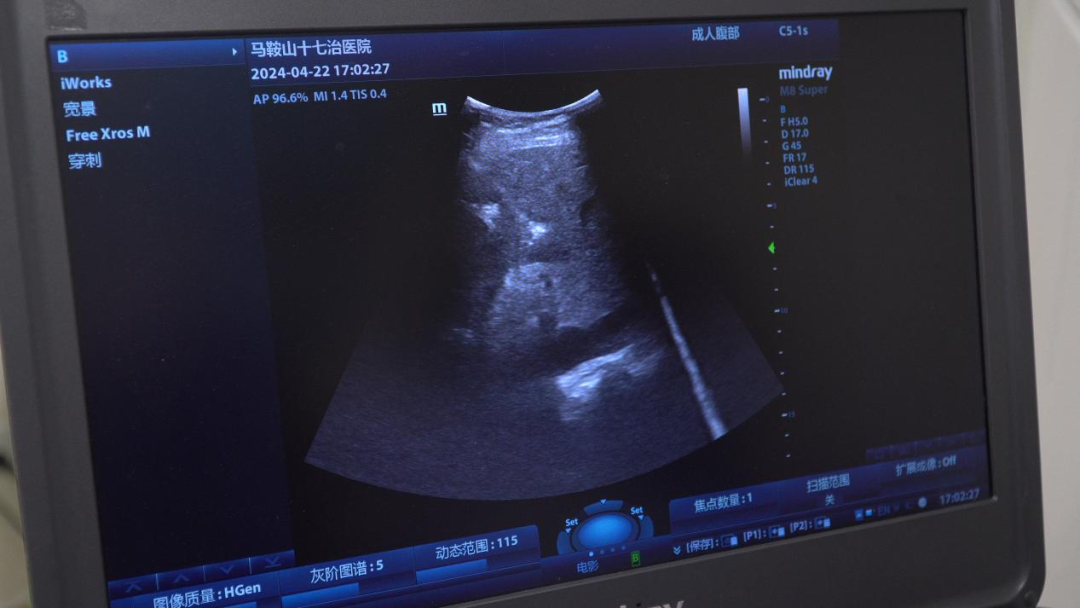

为了提高穿刺阳性率,减少穿刺并发症,我院肿瘤科营磊医生反复研究影像图像,决定采取常规CT利用周边血管等解剖结构标记病灶,进行病灶穿刺引导,到达位置后再用床边B超实时验证针尖可有异常回声,避开周围血管,接着再实时进行穿刺,利用我院现有设备,因地制宜,就地取材,巧妙的人工结合B超和CT的图像融合,最终成功取到病理,病理结果提示阳性结果。